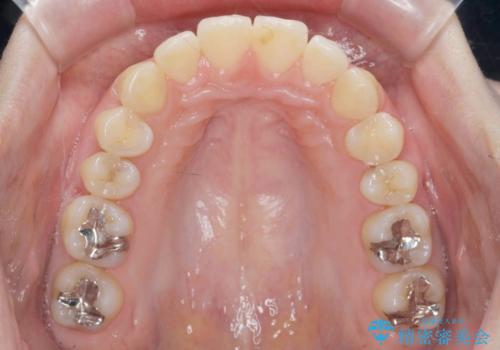

カリエール・マイクロインプラントを用い、時間はかかりましたが大きく歯の後方移動が達成され、前歯の見た目が大きく改善されました。

大きな後方移動を達成するにはマイクロインプラントと日常的なゴムかけが大切です。